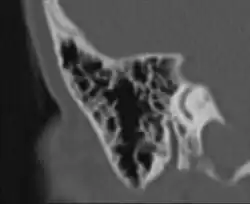

CT-Bild: Stark pneumatisierter Warzenfortsatz von vorne (schwarz = Luft). Sichtbar auch der hintere Bogengang.

Die vom Mittelohr ausgehende Pneumatisation des Schläfenbeines ist mit dem fünften bis sechsten Lebensjahr weitgehend abgeschlossen. Ergebnis dieses Vorganges sind die pneumatischen Zellen, vor allem im Warzenfortsatz (Processus mastoideus). Es sind kleine, von Schleimhaut ausgekleidete Hohlräume, die durch unterschiedlich große Öffnungen miteinander und in der Gesamtheit mit dem Antrum mastoideum und damit mit dem Mittelohr in Verbindung stehen. Das Ausmaß der Pneumatisation des Schläfenbeines kann sehr unterschiedlich sein, es gibt Schläfenbeine mit fast komplett fehlender („gehemmter“) Pneumatisation, was meist als Folge häufiger Mittelohrentzündungen in der Kindheit anzusehen ist. Andererseits kann sich die Pneumatisation weit nach oben in die Schläfenbeinschuppe (Pars squamosa), nach vorne in den Jochbeinfortsatz (Processus zygomaticus) und in die Spitze der Felsenbeinpyramide ausdehnen. Es lassen sich im Warzenfortsatz typischerweise einzelne Zellgruppen oder Zellstraßen unterscheiden, die verschiedene Bezeichnungen tragen, wie Winkelzellen, Schwellenzellen, Terminalzellen usw. Dementsprechend werden bei ausgedehnter Pneumatisation Schuppenzellen (in der Schläfenbeinschuppe), Zygomaticuszellen (im Jochfortsatz), perilabyrinthäre Zellen (um das Labyrinth gelegen) und Pyramidenspitzenzellen unterschieden.